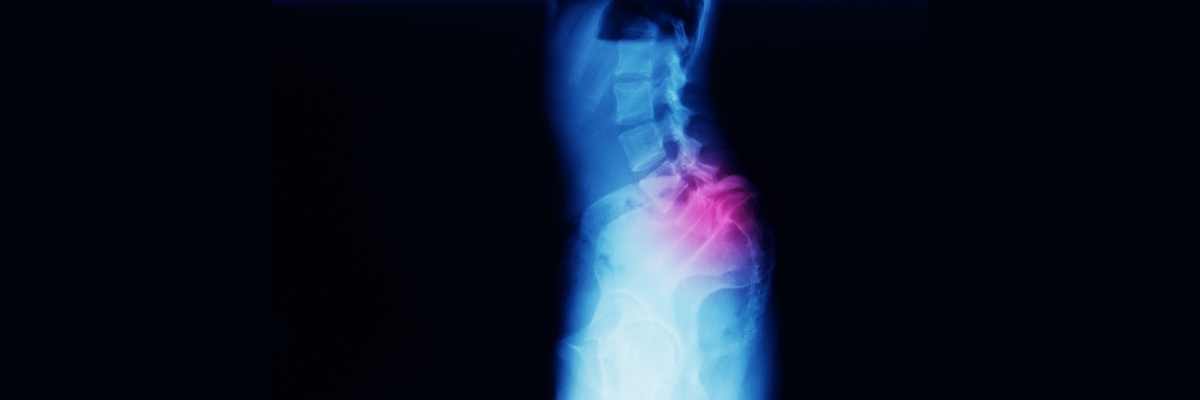

entry image

L5-S1

L5-S1, “lumbosakral eklem” ismiyle de bilinen omurganın bir bölümünü tanımlamak için kullanılan bir terimdir. Bu önemli omurga hareket segmenti, sırtın alt kısmında lomber omurga ve sakral omurganın arasında yer alır. Bir tür geçiş bölgesi olan lumbosakral eklem, özellikle yüklerin omurga üzerinden omurgalara, pelvise ve hatta bacaklara dek aktarılmasına destek olur. Bu alandaki omurga eğriliği genel itibarıyla lomber lordozdan sakral kifozaya doğru değişiklik gösterir. Lomber lordoz öne eğriliği, sakral kifoz ise geriye eğriliği ifade eder.